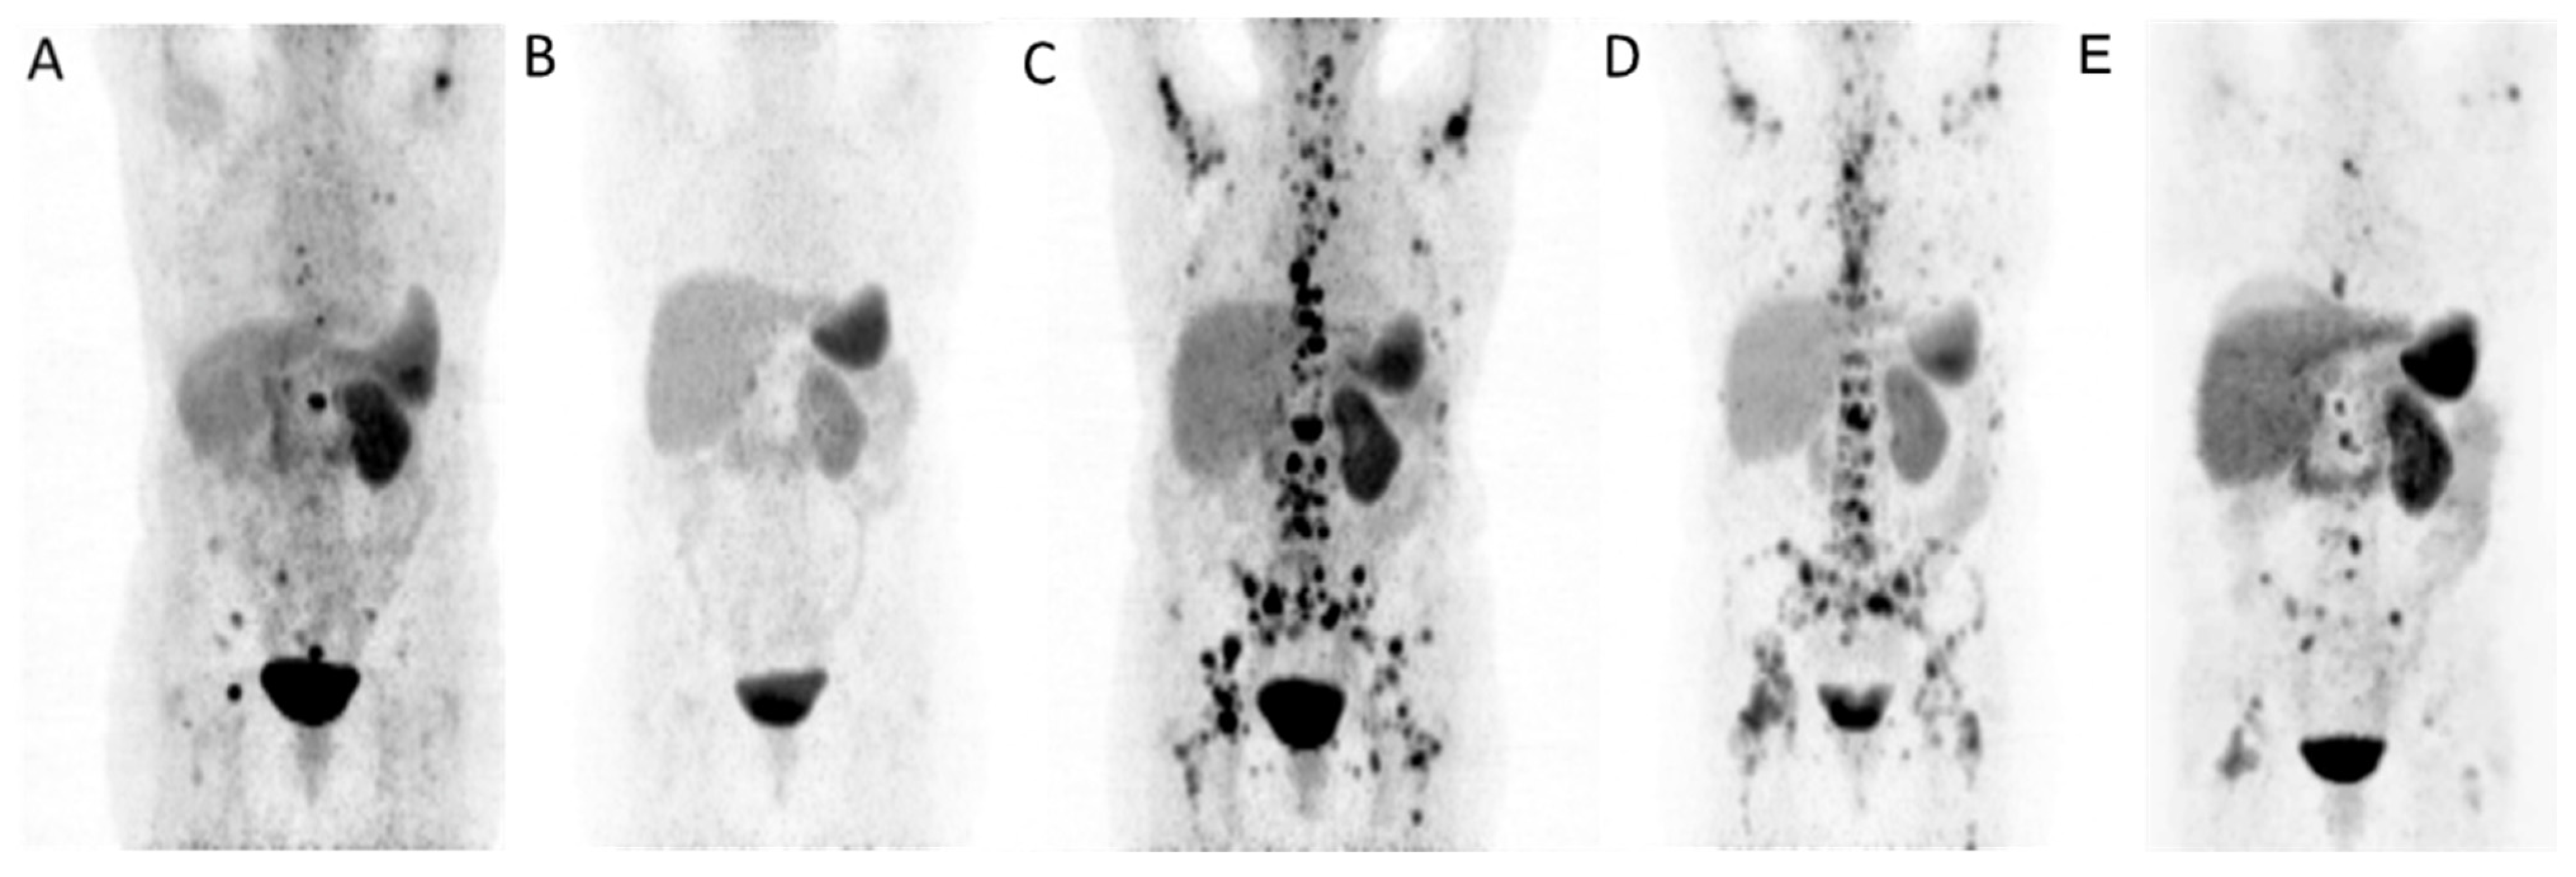

| 60y/w | Ileum/G2 | CTx (Dox/5FU), SSA | liver, bone, LN | G-CSF | Successful | 0 GBq (0) | 43.0 GBq (6) | SD |

| 54y/w | Kidney/G2 | Surgery, SSA, PRRT | bone | G-CSF | Successful | 29.0 GBq (4) | 33.4 GBq (5) | PR |

| 70y/m | Jejunum/G1 | Surgery, SSA, PRRT | liver, bone | G-CSF, Plerixafor | Successful | 15.7 GBq (2) | 5.6 GBq (1) | PD |

| 53y/m | CUP/G2 | CTx (Cis/5FU), Radiation | liver, bone, LN | G-CSF | Successful | 0 GBq (0) | 39.0 GBq (6) | PR |

| 58y/w | Pancreas/G2 | CTx (STZ/5FU), SSA Surgery, PRRT | liver, bone | G-CSF, Plerixafor | Successful | 37.3 GBq (5) | 7.5 GBq (1) | PR |